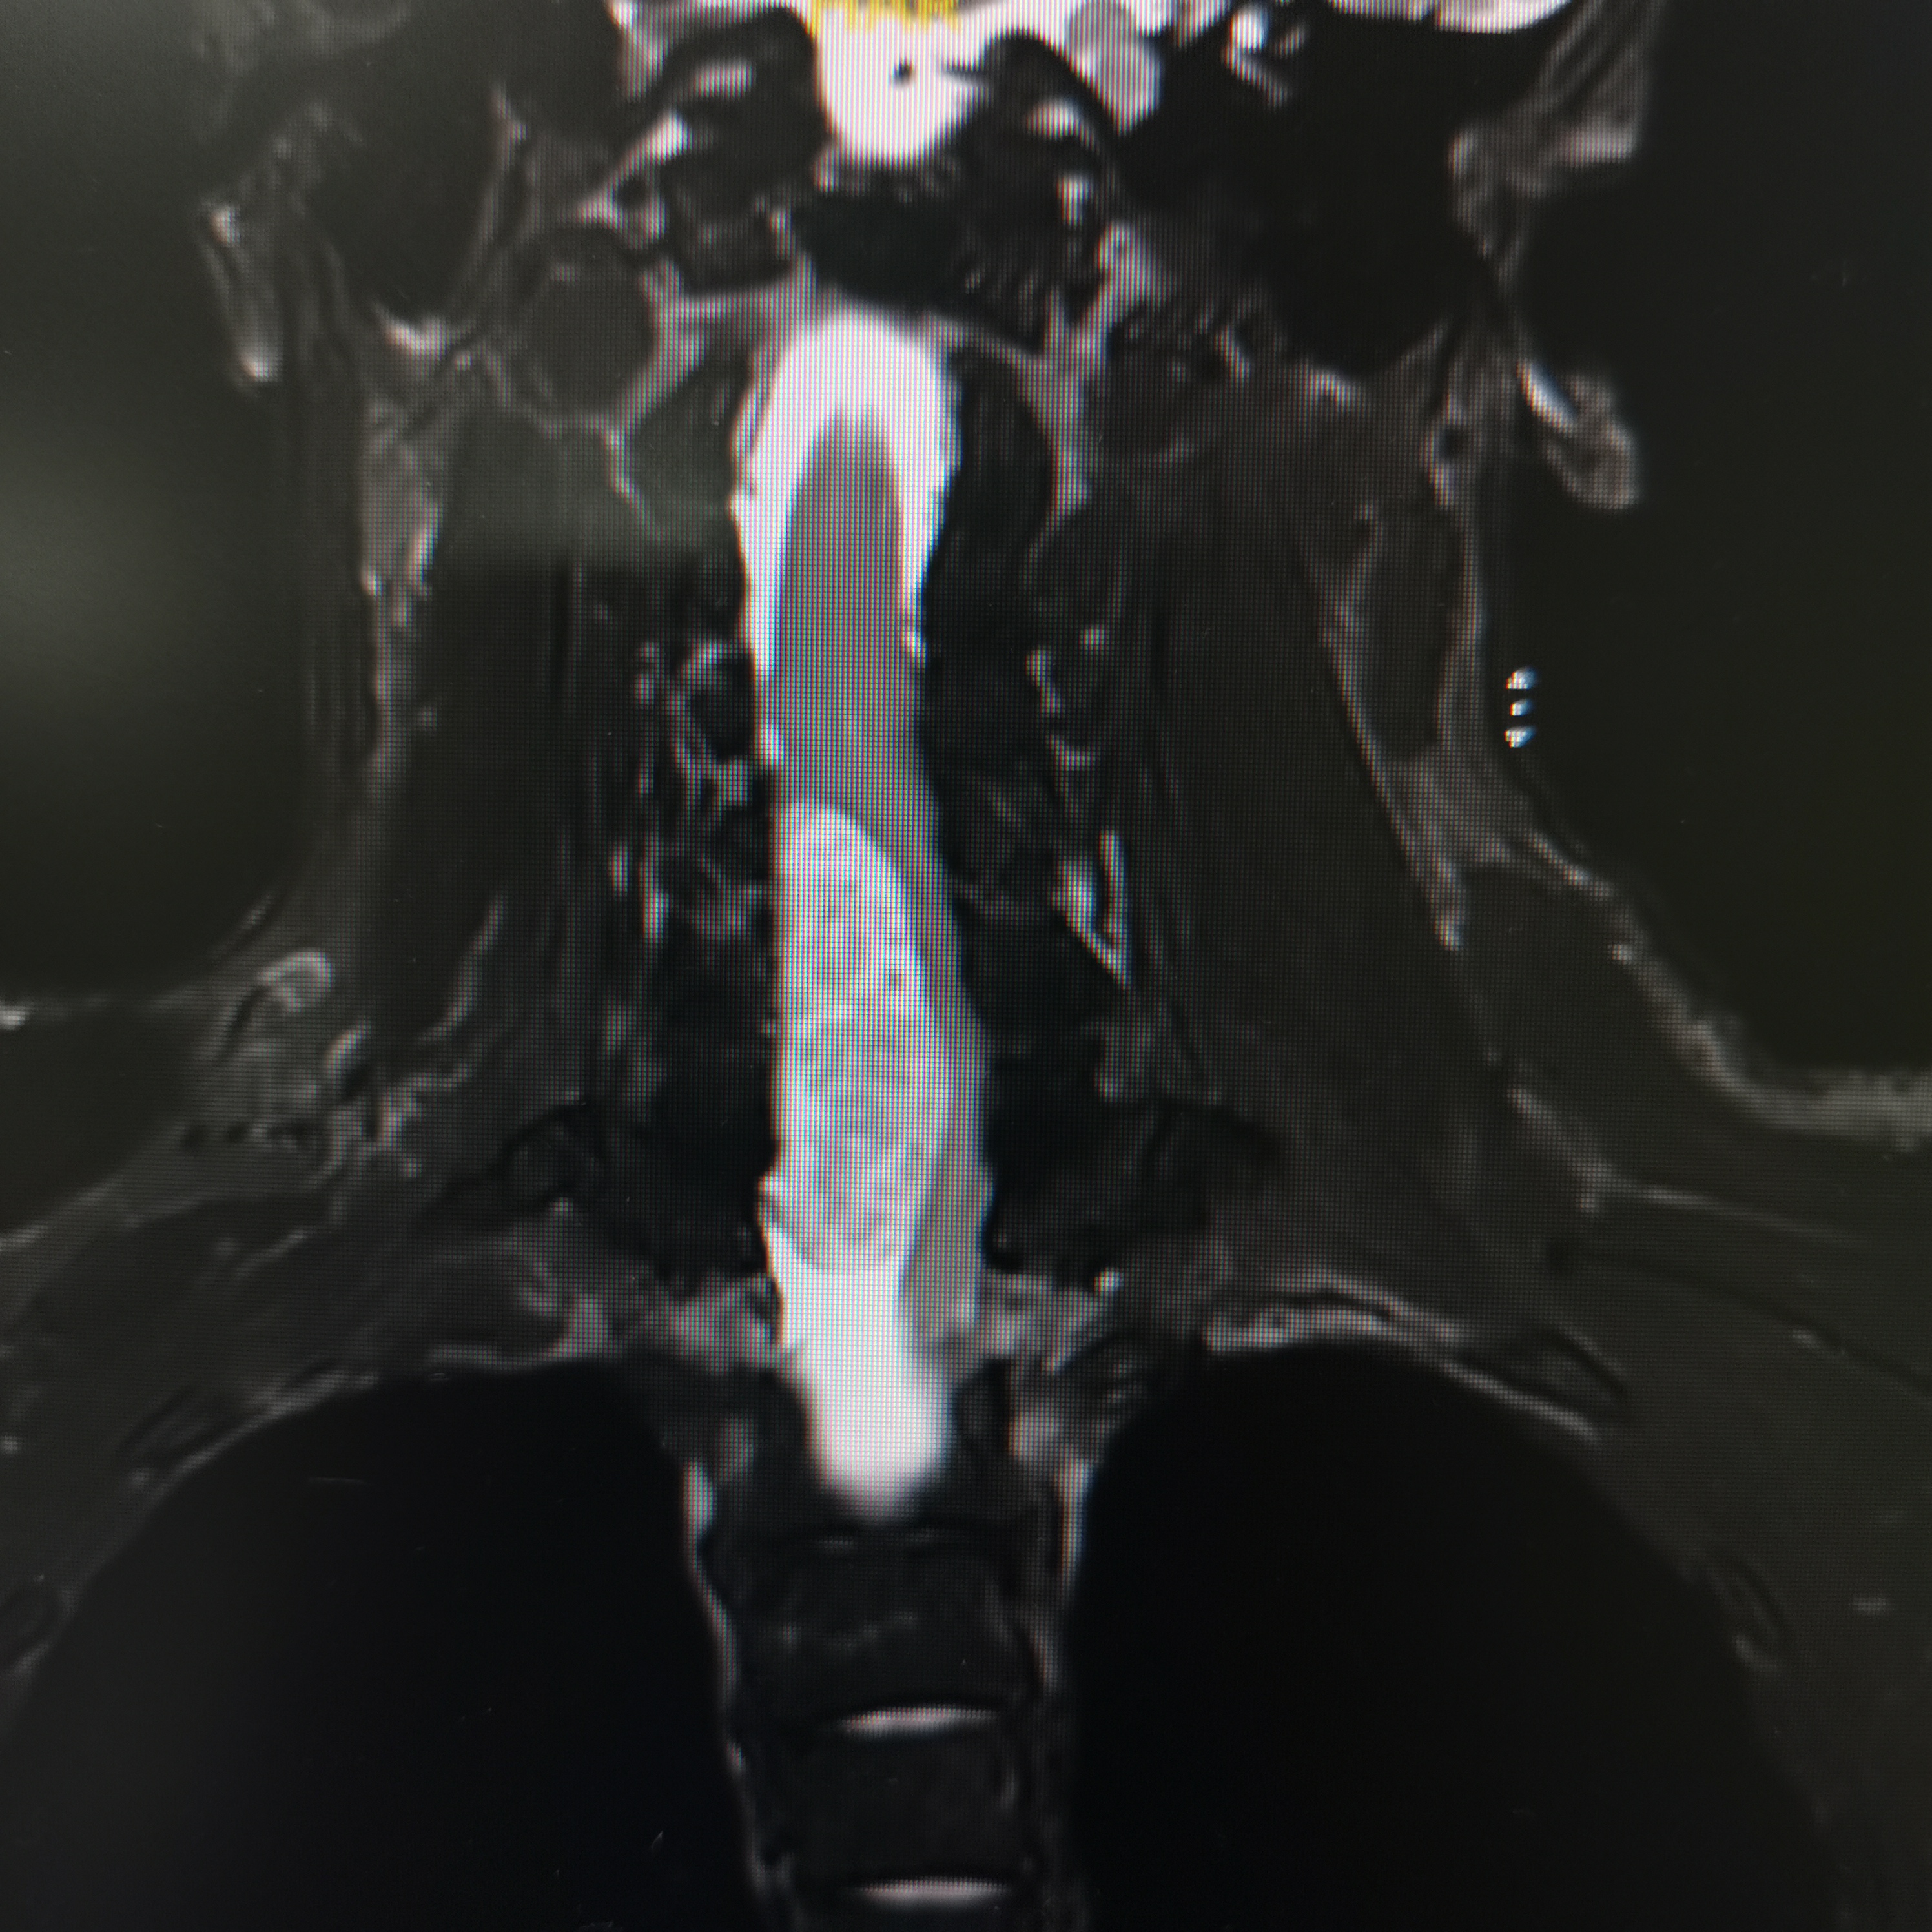

脊髓脊柱-脊髓脊柱肿瘤

神经纤维瘤病的治疗需要综合考虑患者的病情、症状、年龄、身体状况等因素,制定个性化的治疗方案。